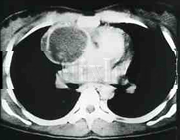

Timoma |